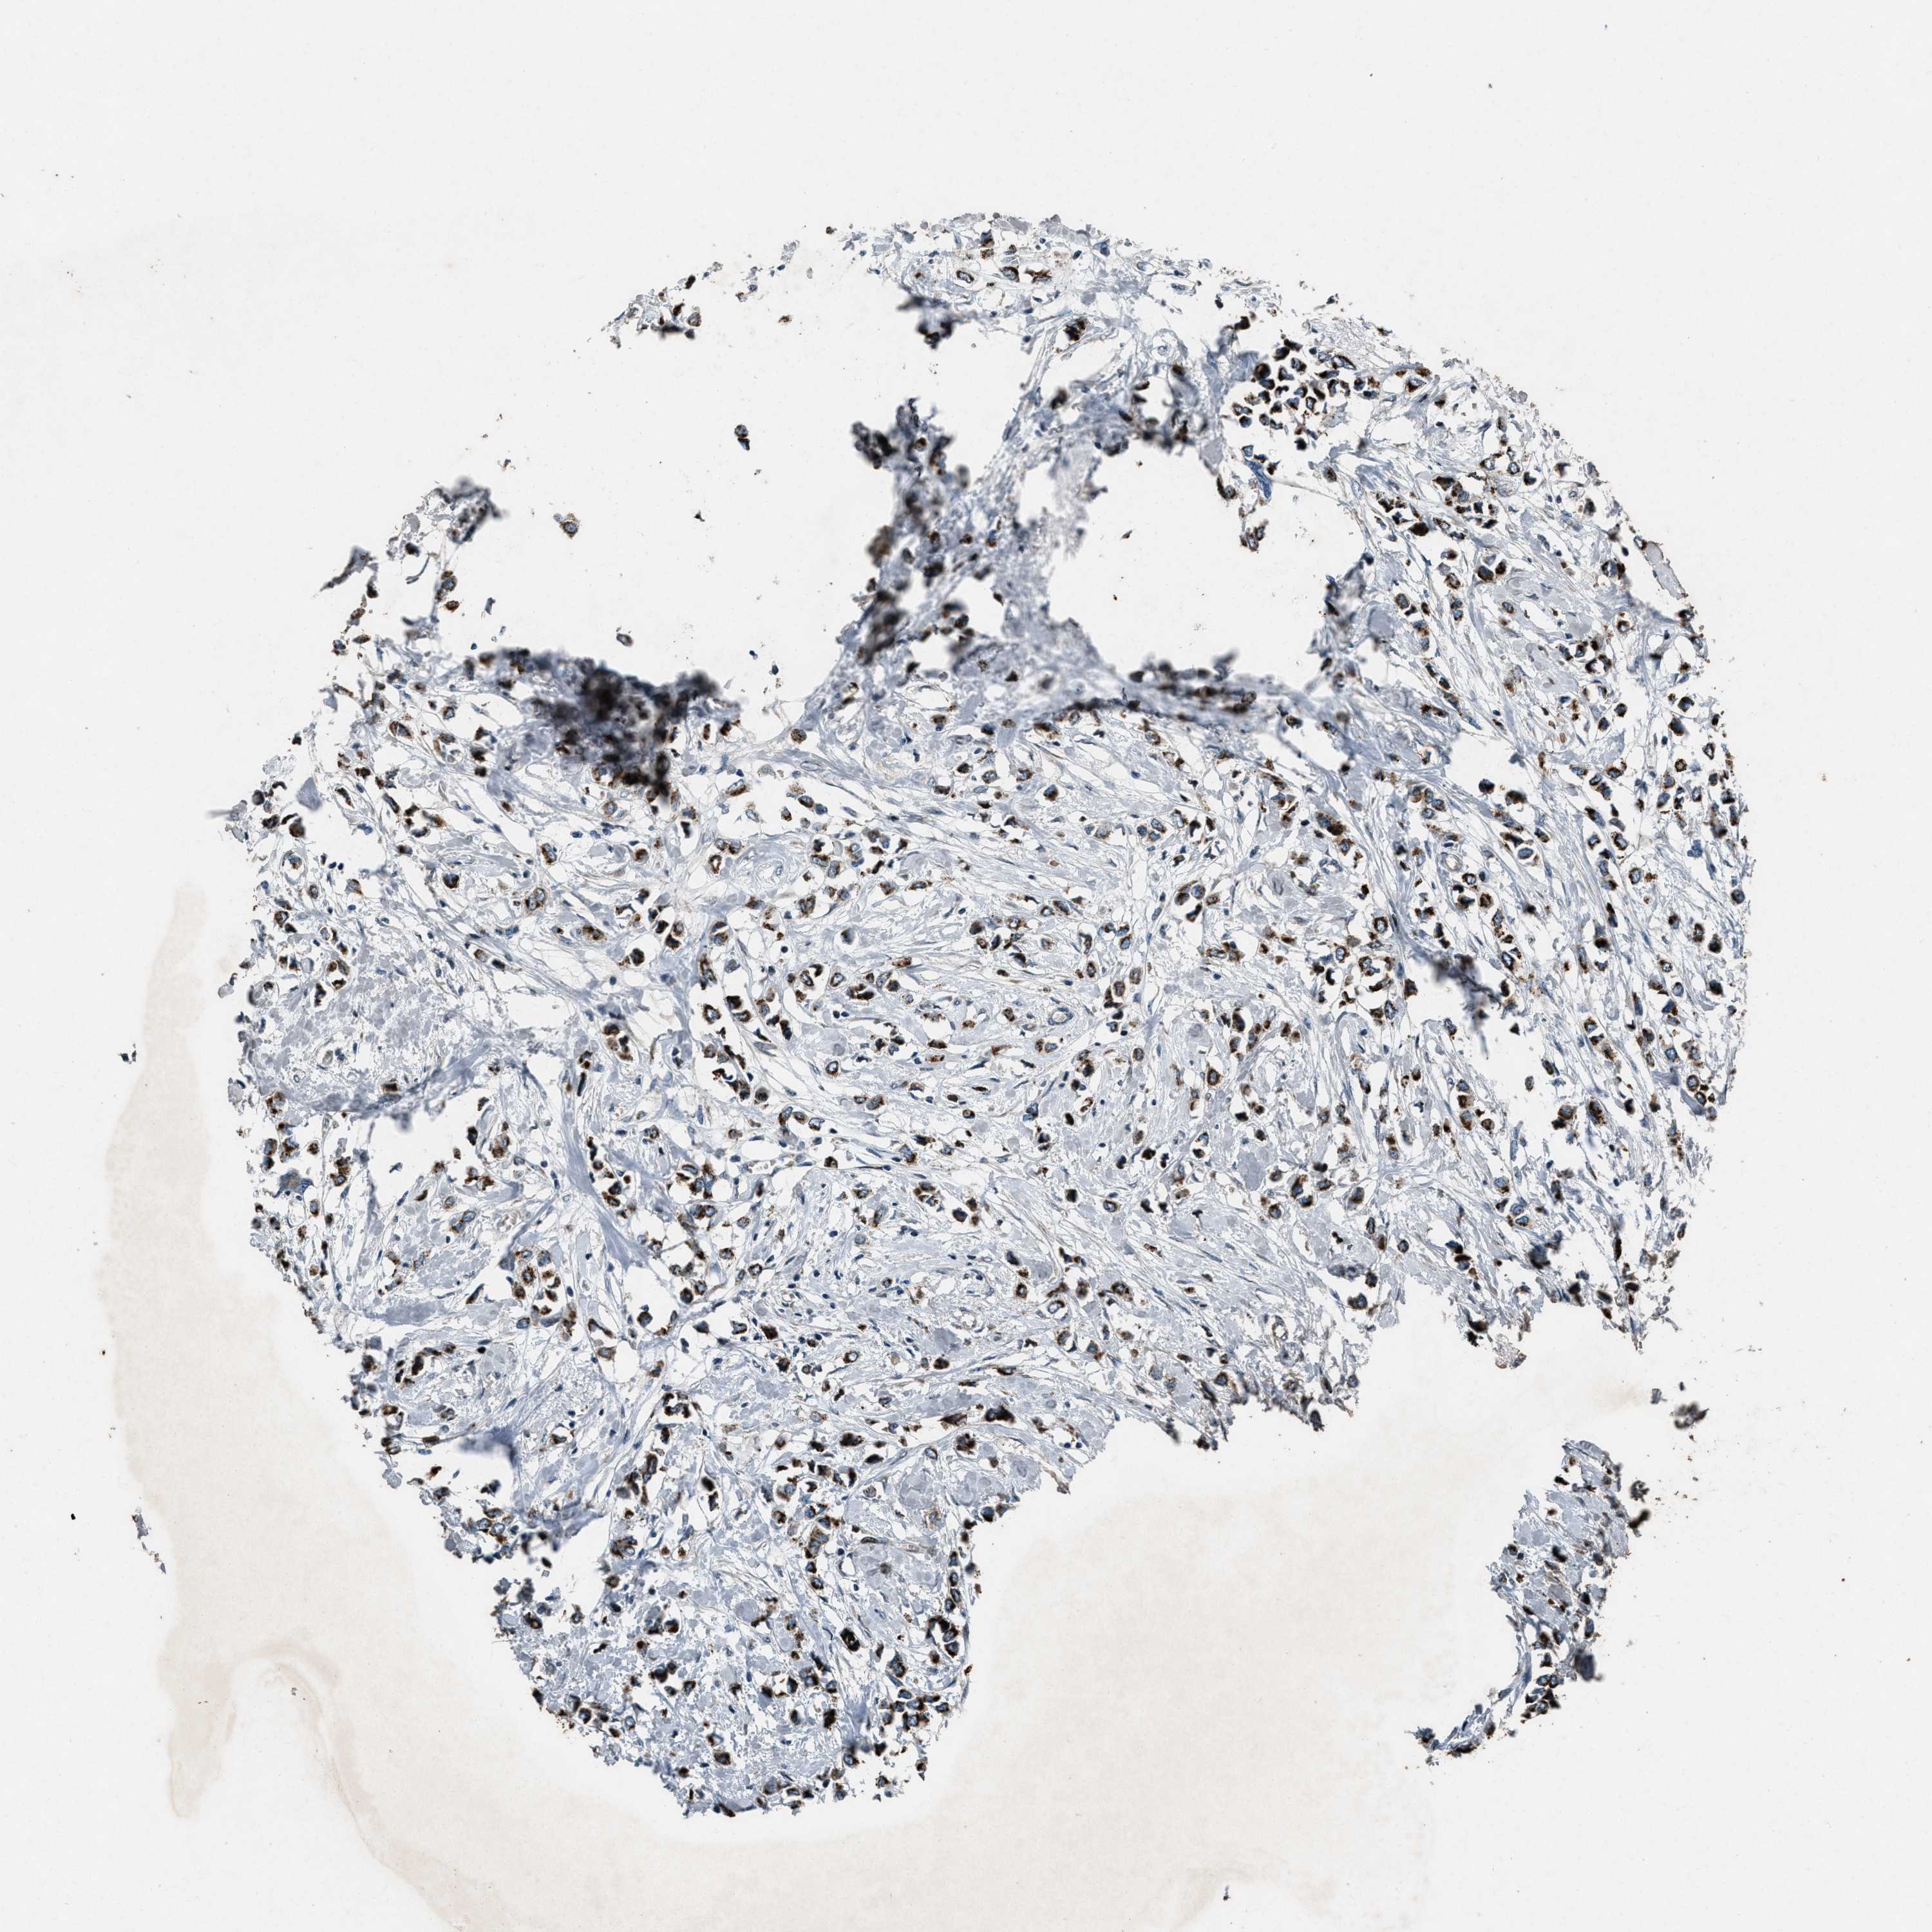

CANCER BREAST CANCER Show tissue menu

BRCA TCGA BRCA VALIDATION PROTEIN EXPRESSION